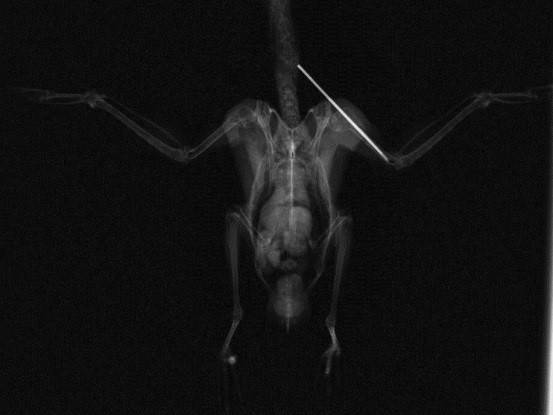

そして注射針を骨髄内に入れて整復した後のレントゲン写真です。

この骨に刺しているものが注射針だったりします。